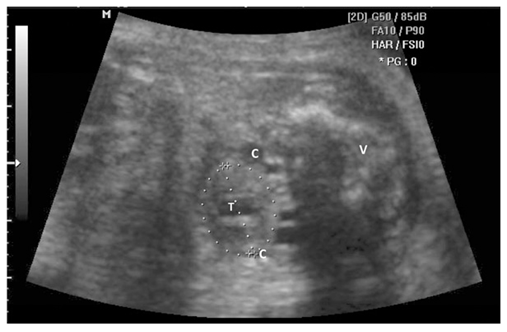

IT Beispielbild

IT / CM / BS Anleitung Messung

IT / CM / BS Tabelle Normwerte